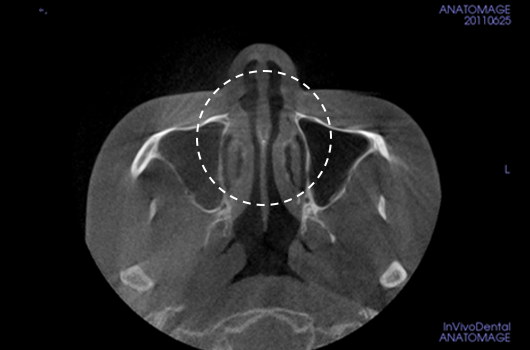

Operasi hidung CT 3D membantu pelaksanaan operasi hidung yang lebih canggih setelah menganalisis wajah secara cermat untuk menentukan mana yang terbaik.Analisis tiga dimensi digunakan untuk mengetahui keadaan secara umum, ukuran, bentuk, dan asimetri tulang hidung, tulang rawan septum hidung, dan jaringan kulit, yang tidak dapat ditentukan melalui konsultasi pada umumnya. Saat merencanakan revisi operasi hidung, kami dapat memeriksa elemen fungsional seperti deviasi septum hidung, bentuk implan yang ada, termasuk implan silikon, atau komplikasi dari operasi sebelumnya.

Pentingnya 3D-CT Scan pada Operasi Hidung

Dalam setiap konsultasi operasi hidung, Klinik Operasi Plastik Braun menggunakan 3D-CT scan untuk menganalisis isu-isu berikut dalam tiga dimensi: Rancangan bedah dapat dibuat lebih tepat dan potensi efek samping dapat berkurang dengan memahami lebih lanjut ukuran, bentuk, dan asimetri bagian hidung yang tak kasat mata dan struktur anatomi disekitarnya sebelum operasi.

1. Analisis tulang rawan septum dalam berbagai ukuran dan bentuk

2. Diagnosis dan tindakan untuk deviasi hidung dan deviasi septal

3. Analisis untuk lebar dan asimetri tulang hidung

4. Diagnosis Inferior turbinate asymametry dan pembedahan hidung tersumbat